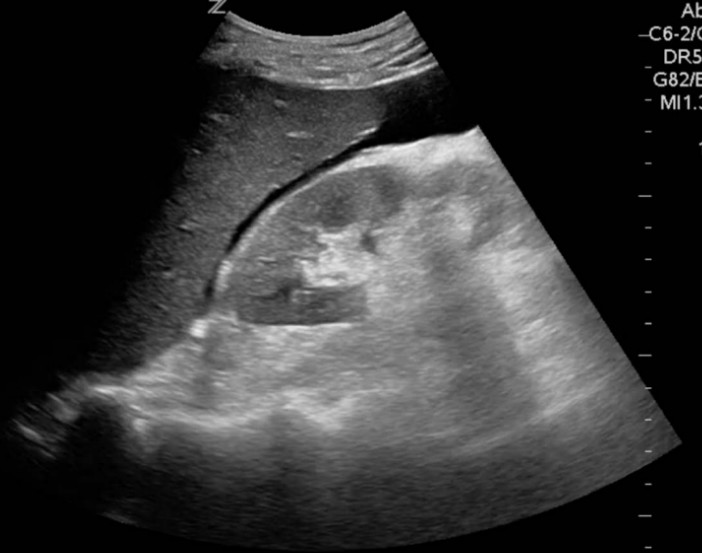

An image from the RUQ view of his FAST scan is provided.

2. Interpret the FAST scan image. 1 mark